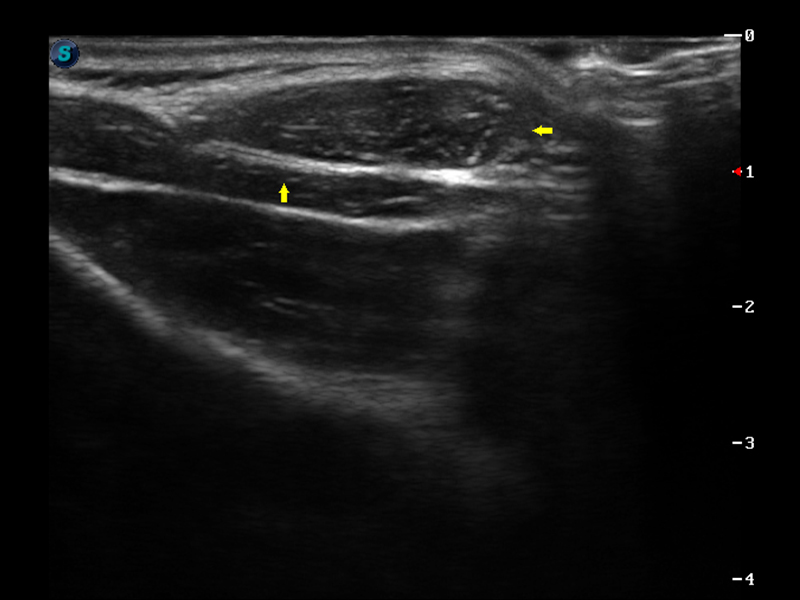

μ-Scan微米成像

弹性成像